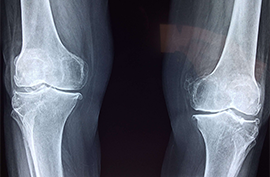

Joints Replacement

Knee Replacement

Osteoarthritis